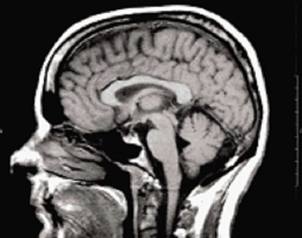

Identifican genes vitales en la actividad cerebral.

El grupo de genes que fue hallado sólo se encuentra en mamíferos y son esenciales para proporcionar la energía que requieren las neuronas. Un equipo del Instituto de Investigación Biomédica de Barcelona (IRB),...